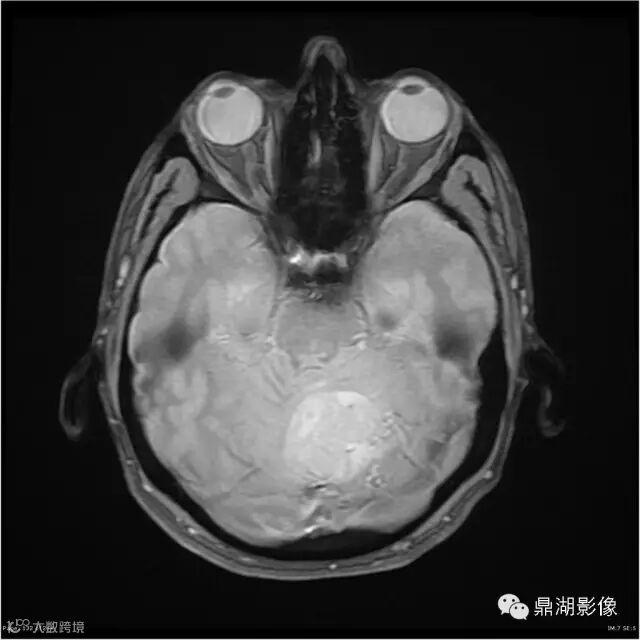

Axial T2WI

影像:可见一个约43 x 36 x 31mm的从小脑蚓部延伸而来的占位,T1WI、T2WI呈高低混杂信号,病灶周边见流空血管影及水肿带,增强病灶明显强化,中心见无明显坏死区,它紧靠左小脑幕上。第四脑室受压变窄,室管膜水肿,可见脑桥及延脑扁桃体进入枕骨大孔。

本例为一例实质性血管母细胞瘤。实性血管母细胞瘤CT平扫示病灶呈等或高密度,增强后可见明显强化。MRI平扫通常病灶很不均质,T1呈稍低信号为主的较混杂信号,T2呈等、高信号,DWI通常呈低信号或等信号。文献报道,实性血管母细胞瘤较典型的表现为瘤内及瘤周扩张的流空血管影,瘤周中、重度水肿。因此,小脑半球区的单发肿块伴流空血管影,周围大片水肿以及增强后肿块明显强化"形态规则"边界清楚,此时应将实性血管母细胞瘤考虑在内。